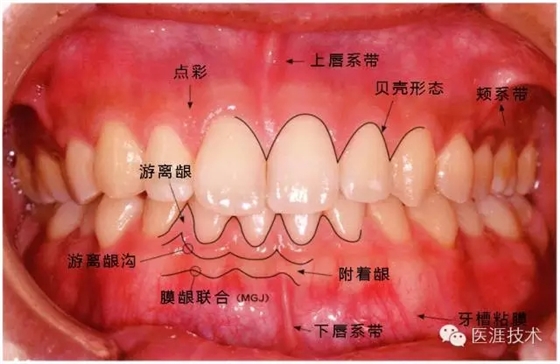

健康牙周組織的牙齦邊緣呈珊瑚粉,邊緣牙齦略呈圓弧狀。牙間可見三角形的牙間乳頭,牙齦邊緣相連呈貝殼形。

附著齦與游離齦相連時,有時有游離齦溝存在(成人的30~40%)。

附著齦通過膠原纖維牢固結(jié)合骨骼與牙骨質(zhì),因此可見不可動、硬而緊繃的點彩(橘皮樣點狀凹凸)。

從牙齦牙槽粘膜到根尖有牙槽粘膜。牙槽粘膜為暗紅色,與骨骼結(jié)合較松,故可動。

健康且正常的牙周組織臨床圖像